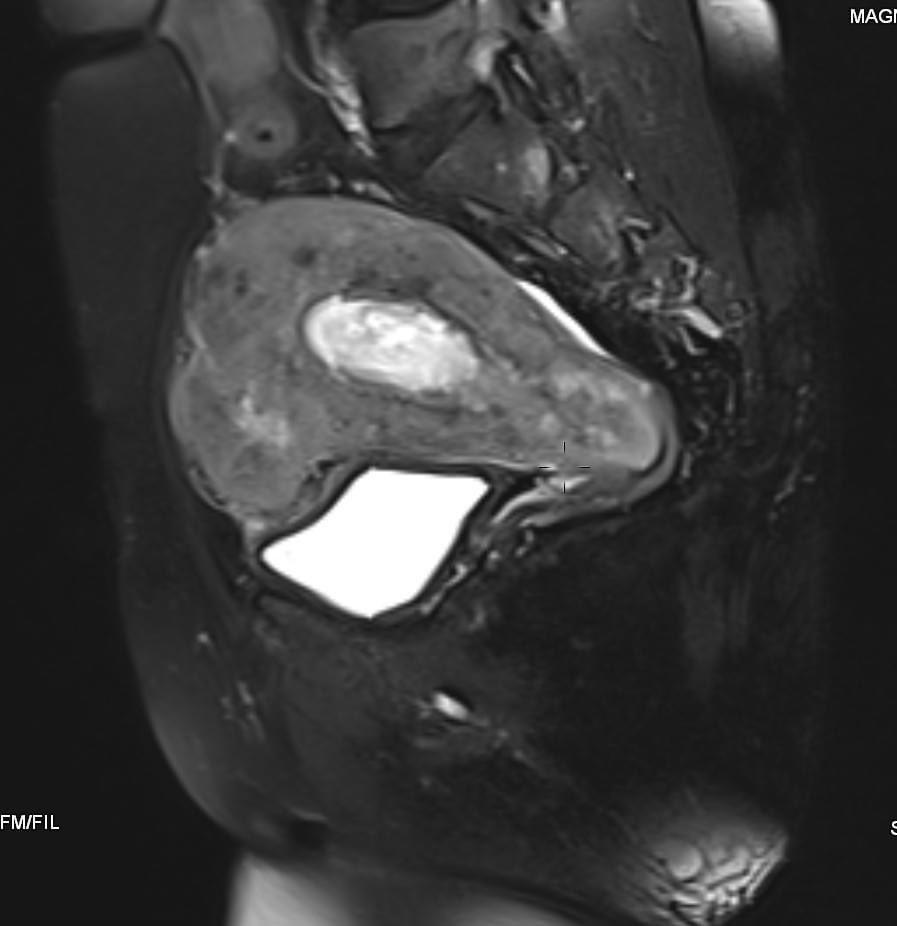

58-year-old female with active vaginal bleeding #Findings: •There is thickening of the endometrium measuring 14mm in thickness with internal intermediate signal intensity seen. •The lesion is seen extending into the myometrium with invasion of the serosa layers. •The lesion

hemo_shk's tweet image. 58-year-old female with active vaginal bleeding

#Findings:

•There is thickening of the endometrium measuring 14mm in thickness with internal intermediate signal intensity seen.

•The lesion is seen extending into the myometrium with invasion of the serosa layers.

•The lesion

- 58-year-old female with vaginal bleeding for the past 2 months - findings and diagnosis ? #MEDHM @IhabFathiSulima #MedEd #MedX

hemo_shk's tweet image. - 58-year-old female with vaginal bleeding for the past 2 months

- findings and diagnosis ?